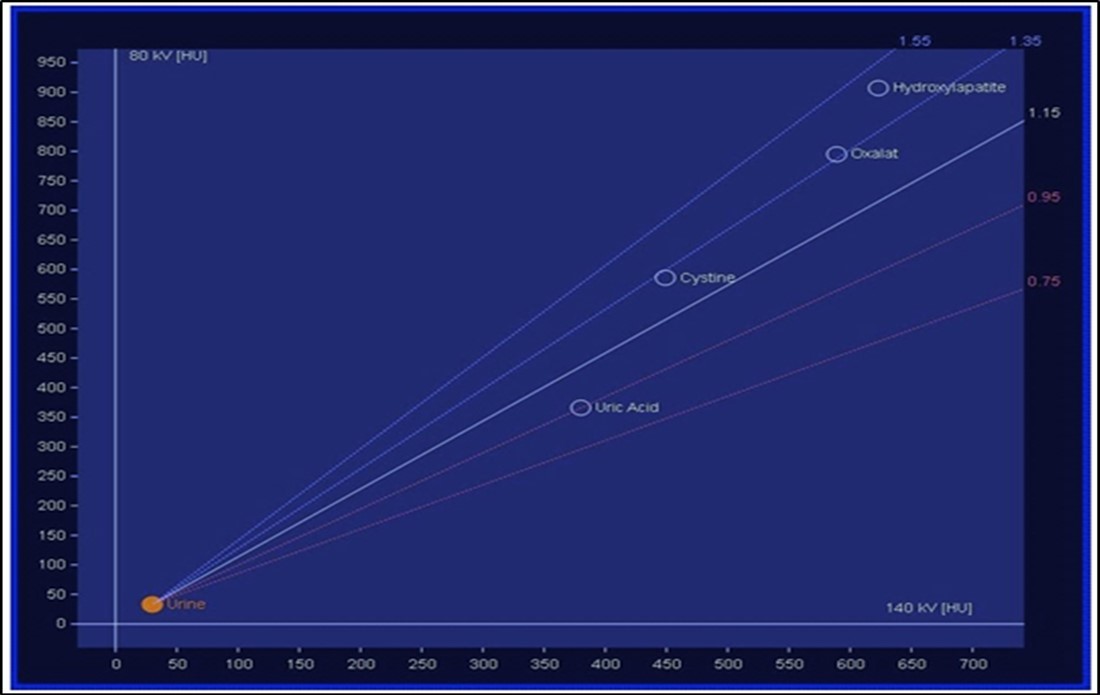

The attenuation difference is shown in colors. In graph 1, the 1.15 ratio represents threshold between uric acid and other stones. If a data point corresponding to a stone with unknown composition falls below this line, the algorithm will characterize such stone as a UA stone and will assign it a predefined red color. And if it falls above the line it will be identified as a non-UA stone and will be shown blue 2.

Stone analysis, together with serum and 24-hour urine metabolic evaluation, can identify the etiology in more than 95% of patients 1. Preoperative prediction of stone type (figure 1 and figure 2) is crucial for therapeutic decision making and follow-up 2, 3, 4, 5, 6. Some studies have reported predictive role of dual energy CT scan for determination of stone type 7, 8, 9.